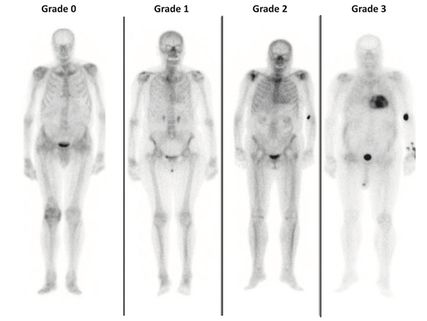

Knochenszintigrafie: PYP/DPD-Scan

Abb. 5:Knochenszintigrafie mit Perugini-Score 0 (links) bis 3 (rechts; aus Garcia-Pavia P et al. 2021)9

Bei Verdacht auf kardiale Speichererkrankung/Amyloidose sollte eine Knochenszintigrafie mit Bestimmung des Perugini-Scores erfolgen (Abb.5).9 Dieser semiquantitative Score ermöglicht (bei Grad 2/3) die Diagnose einer ATTR-Amyloidose ohne histologische Gewebebeurteilung oder kann diese ausschließen (Grad 0). Im Falle eines Perugini Grad 1 ist eine weitere Abklärung über ein Zentrum indiziert. Zu beachten ist, dass die Knochenszintigrafie nicht verlässlich zwischen ATTR- und AL-Amyloidose unterscheiden kann. Aus diesem Grund müssen immer auch eine Elektrophorese und Immunfixation in Serum und Harn durchgeführt werden.13